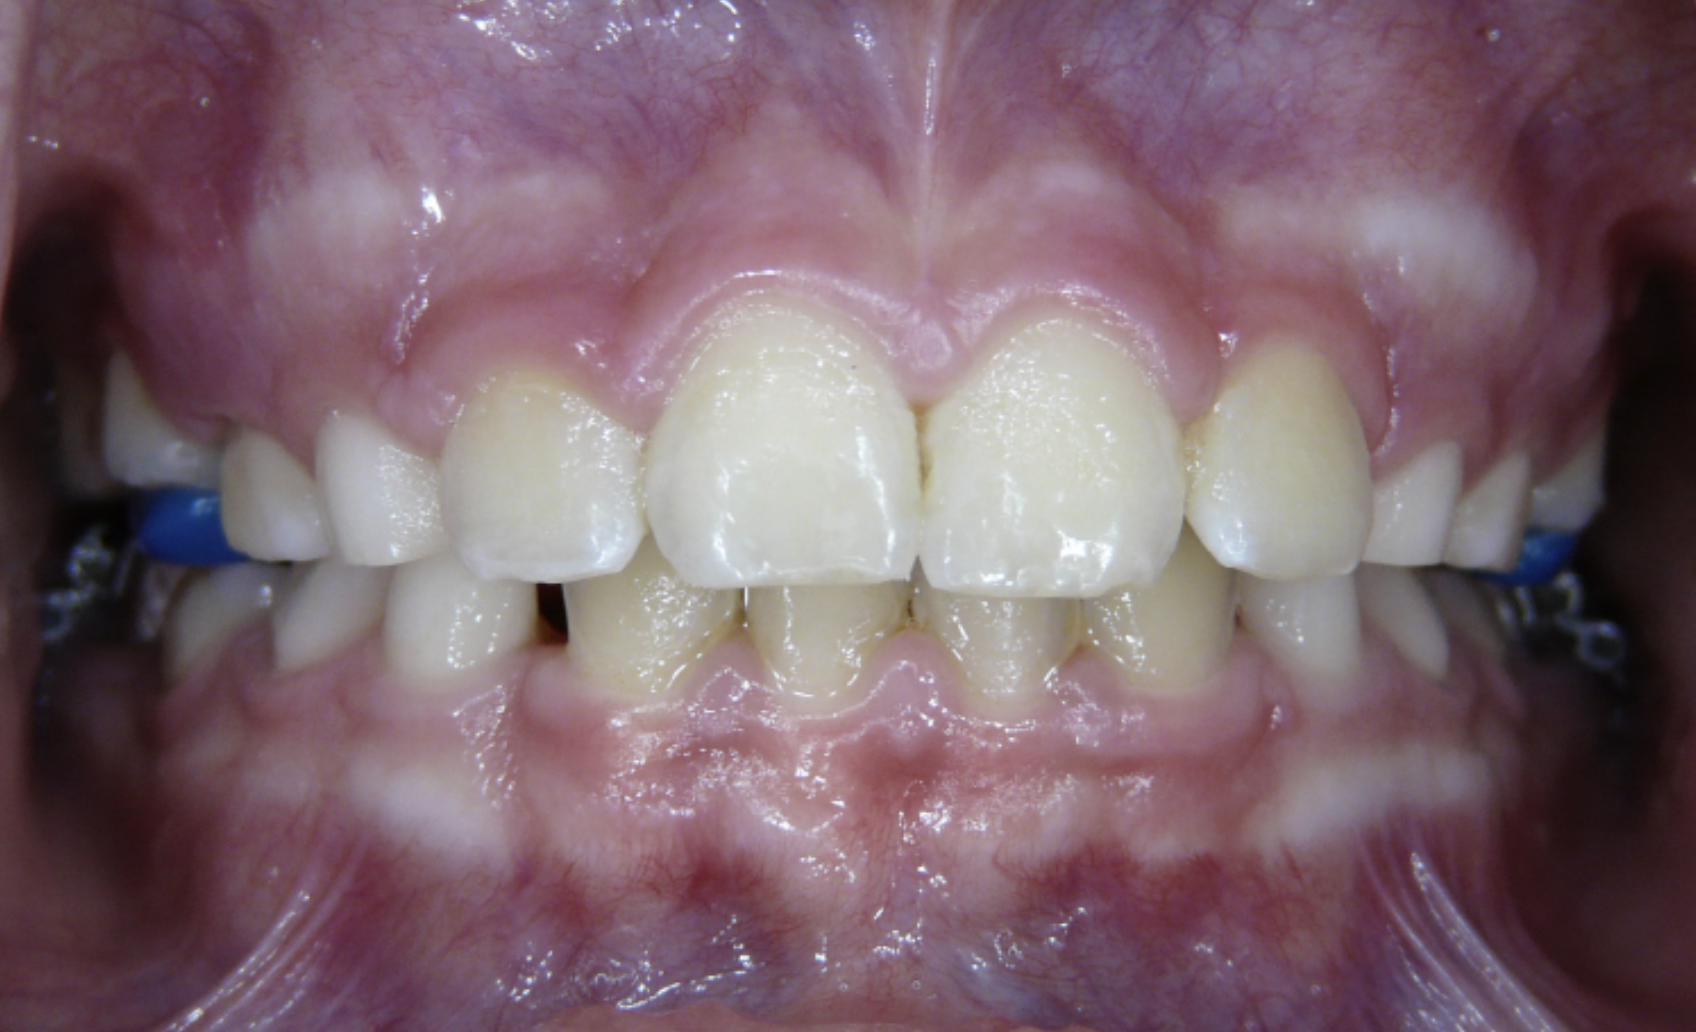

Protrusion

Upper teeth stick out beyond the lower teeth.